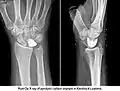

Fig 2. Kienbocks x-ray

Kienbock’s Disease is defined as avascular necrosis of the lunate (Cross & Matullo, 2014, p. 141). The direct cause of Kienbock’s disease is largely unknown (Almquist, 1986, Nathan & Meadows, 1987) however, studies have confirmed an association between negative ulnar variance and the development of Kienbock’s Disease (Bonzar et al., 1998, Mirabello, Rosenthal, & Smith, 1987). Subjective information shows that ROM tests and palpation cause the patient a large amount of pain. It was identified that the most comfortable position for the client to be in is a supported, resting position. This is supported by Rizzo (2008, p. 491) by stating that avascular necrosis of the carpus is an important cause of wrist pain, limited motion, and weakness.